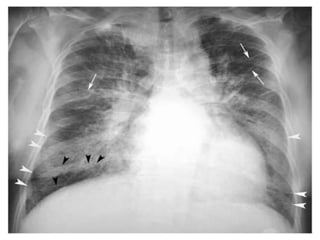

 Chest radiographs show peribronchial thickening, prominent

vascular markings in the upper lung zones, and Kerley B lines.

 As the pulmonary edema worsens, alveoli fill with fluid; the

chest radiograph shows patchy alveolar filling, typically in a

perihilar distribution, which then progresses to diffuse alveolar

infiltrates.

Distinguishing features inX ray …..

 Cardiogenic cause

  Cardiomegaly

  Kerley B lines and loss

of distinct vascular

margins

  Cephalization:

engorgement of

vasculature to the apices

  Perihilar

alveolar infiltrate

  Pleural effusion

 Non cardiogenic cause

  Heart size is normal

  Uniform

  pleural

effusion is

uncommon

  lack of cephalization